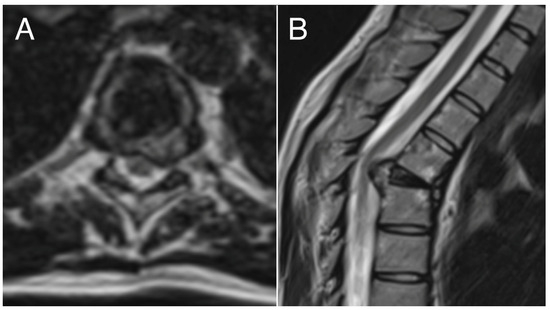

Surgical decompression and stabilization procedures for patients with metastatic spine tumors have been well supported since the publication of the Patchell study in 2005. A parallel body of literature has also grown to support en bloc resection for primary spinal tumors (such as chordoma). As surgeons incorporate these recommendations, it is critical to consider the recent advances in radiation and chemotherapy.